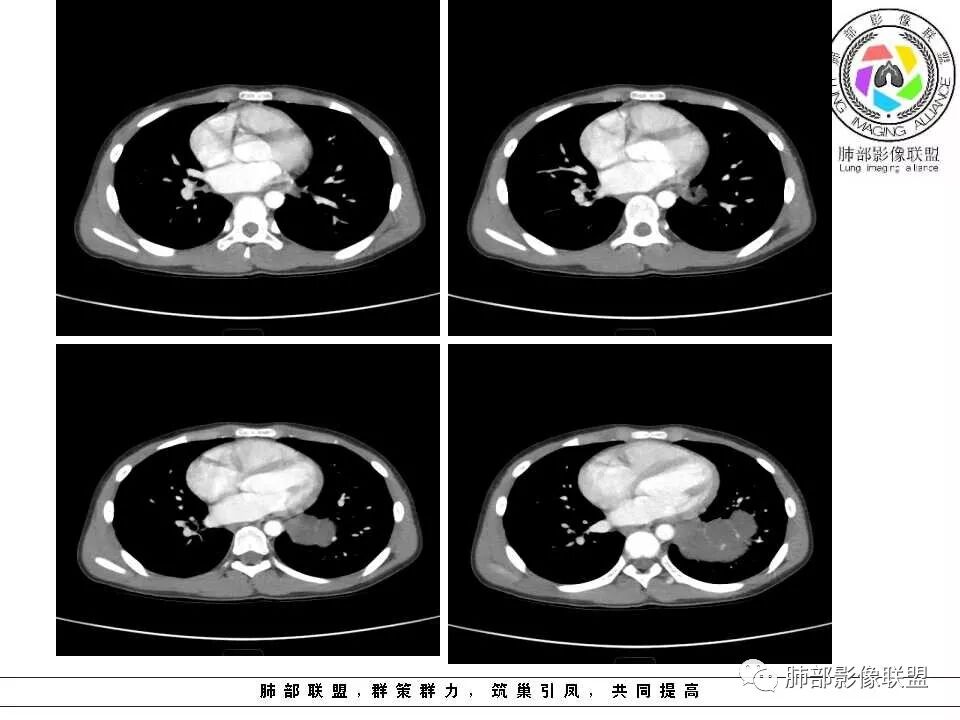

病例提供:运城市第二医院  王崇军

肺隔离症,供血动脉来源腹主动脉

肺隔离症 膈下腹主动脉供血 肺静脉引流 多房改变支气管扩张积液?

左下肺囊性占位,多发分隔,增强分隔及边缘强化,腹主动脉供血,考虑肺隔离征。

儿童左下肺囊性占位,多发分隔,增强分隔可见强化,腹主动脉供血,肺隔离征。

左肺下叶病灶,囊性为主,内见分隔,边界清晰,首先考虑良性病变,增强可见体循环供血,考虑肺隔离症

儿童,左下病变,边界清,囊性,分隔明显,体循环供血,肺隔离症。

左下肺囊性变,内有分隔,体循环供血,支持隔离症。

病灶位于左肺下叶,边界清,囊性,内见分隔,增强可见体循环供血,支持肺隔离症。

左下肺囊性团块灶,多发分隔,增强分隔及边缘强化,主动脉供血,考虑肺隔离症,叶外型。

左下肺囊状影,内有分隔,体循环供血(腹主动脉),肺静脉回流,考虑隔离症

左肺下叶多房囊性病灶,主动脉分支供血,肺静脉回流,符合肺段隔离症,应该是肺外型吧

左肺下叶囊性占位,腹主动脉供血,肺动脉引流,考虑肺隔离症。

左肺下叶囊性变,可见多发分隔,增强后分隔及边缘可见强化,并可见降主动脉分支进入,考虑叶外型肺隔离症

左下肺肿块,内部见多分隔,囊性密度,增强见腹主动脉分支、肺动脉供血,考虑肺隔离症,鉴别支气管囊肿

儿童,左下肺多房囊性占位,增强分隔强化,腹主动脉供血,肺隔离征。

11岁男患,左肺下叶见囊性病变,期内见分隔,增强扫描见强化,供血血管清晰,考虑肺隔离症,不除外多房性囊性病变。

男,11岁,左肺下叶囊性包块,形态不规则,内有分隔,包膜及分隔明显强化,主动脉供血,肺静脉引流,基底段支气管显示不清,首先考虑常见病肺隔离症,支气管囊肿不排除

电话随访,患者在西安某医院手术,为肺隔离症,供血两支动脉,均来自腹主动脉,引流入肺静脉。